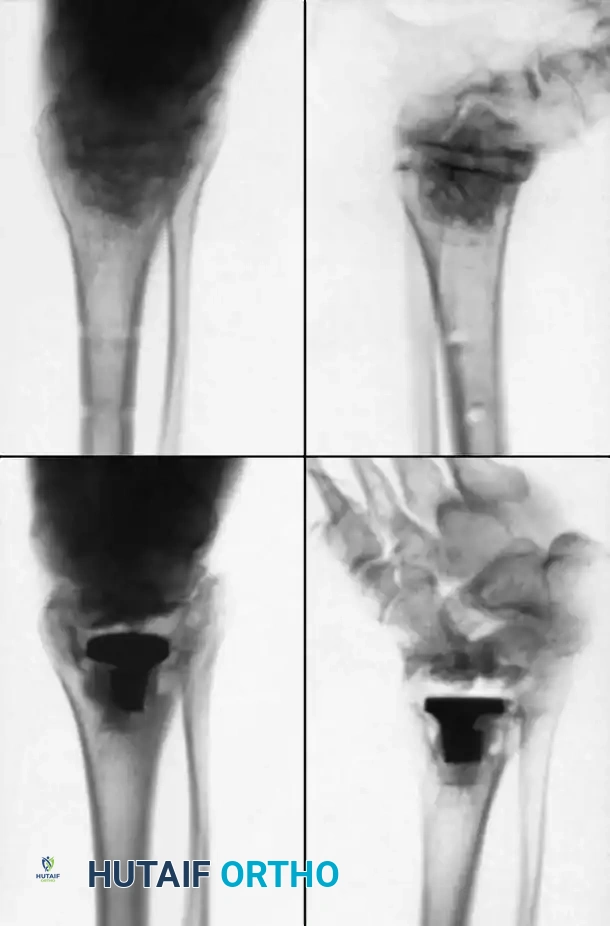

Internal fixation is currently the preferred method for uncomplicated ankle arthrodesis due to higher union rates, superior patient comfort, and the elimination of pin-tract infections. Biomechanical studies demonstrate that crossed, large-diameter (6.5 mm or 7.3 mm) cannulated cancellous screws provide exceptional resistance to shear and torsional forces.

A standard construct involves two or three screws:

1. A "home run" screw directed from the posterior malleolus into the anterior neck of the talus.

2. A screw from the medial malleolus into the lateral body of the talus.

3. A screw from the anterolateral tibia into the medial talar body.

In cases of severe osteopenia or when extending the fusion to the subtalar joint (Tibiotalocalcaneal Arthrodesis), retrograde intramedullary nailing provides a load-sharing construct with superior bending stiffness.